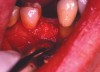

The patient was scheduled for extraction of the tooth, along with socket preservation. After extraction, the socket was curetted. Bone loss on the buccal aspect as a result of infected tissue was noted (Figure 2B). After socket curettage, the socket was grafted using a combination of freeze-dried bone allograft combined with a calcium sulfate bone graft barrier (Figure 2C). The patient was placed on antibiotic and anti-inflammatory medications. Six months after the socket preservation procedure, the site was prepared for implant placement. At the time of implant placement, a core of bone was harvested from the socket preservation site and analyzed histologically (Figure 2D and Figure 2E).

Figure 2b  After extraction of the tooth, the socket was curetted. It was noted that there was bone loss on the buccal aspect because of the presence of infected tissue.

Figure 2c  The socket was grafted using a combination of freeze-dried bone allograft and a calcium sulfate bone graft barrier.